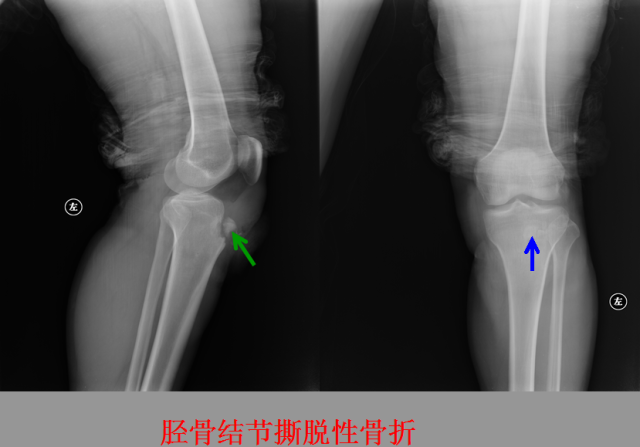

骨折篇

01

定义:骨折{Fracture}是指骨的完整性和连续性的折裂或粉碎。包括创伤性骨折、疲劳性骨折和病例理性骨折。 临床上以创伤性骨折*常见。